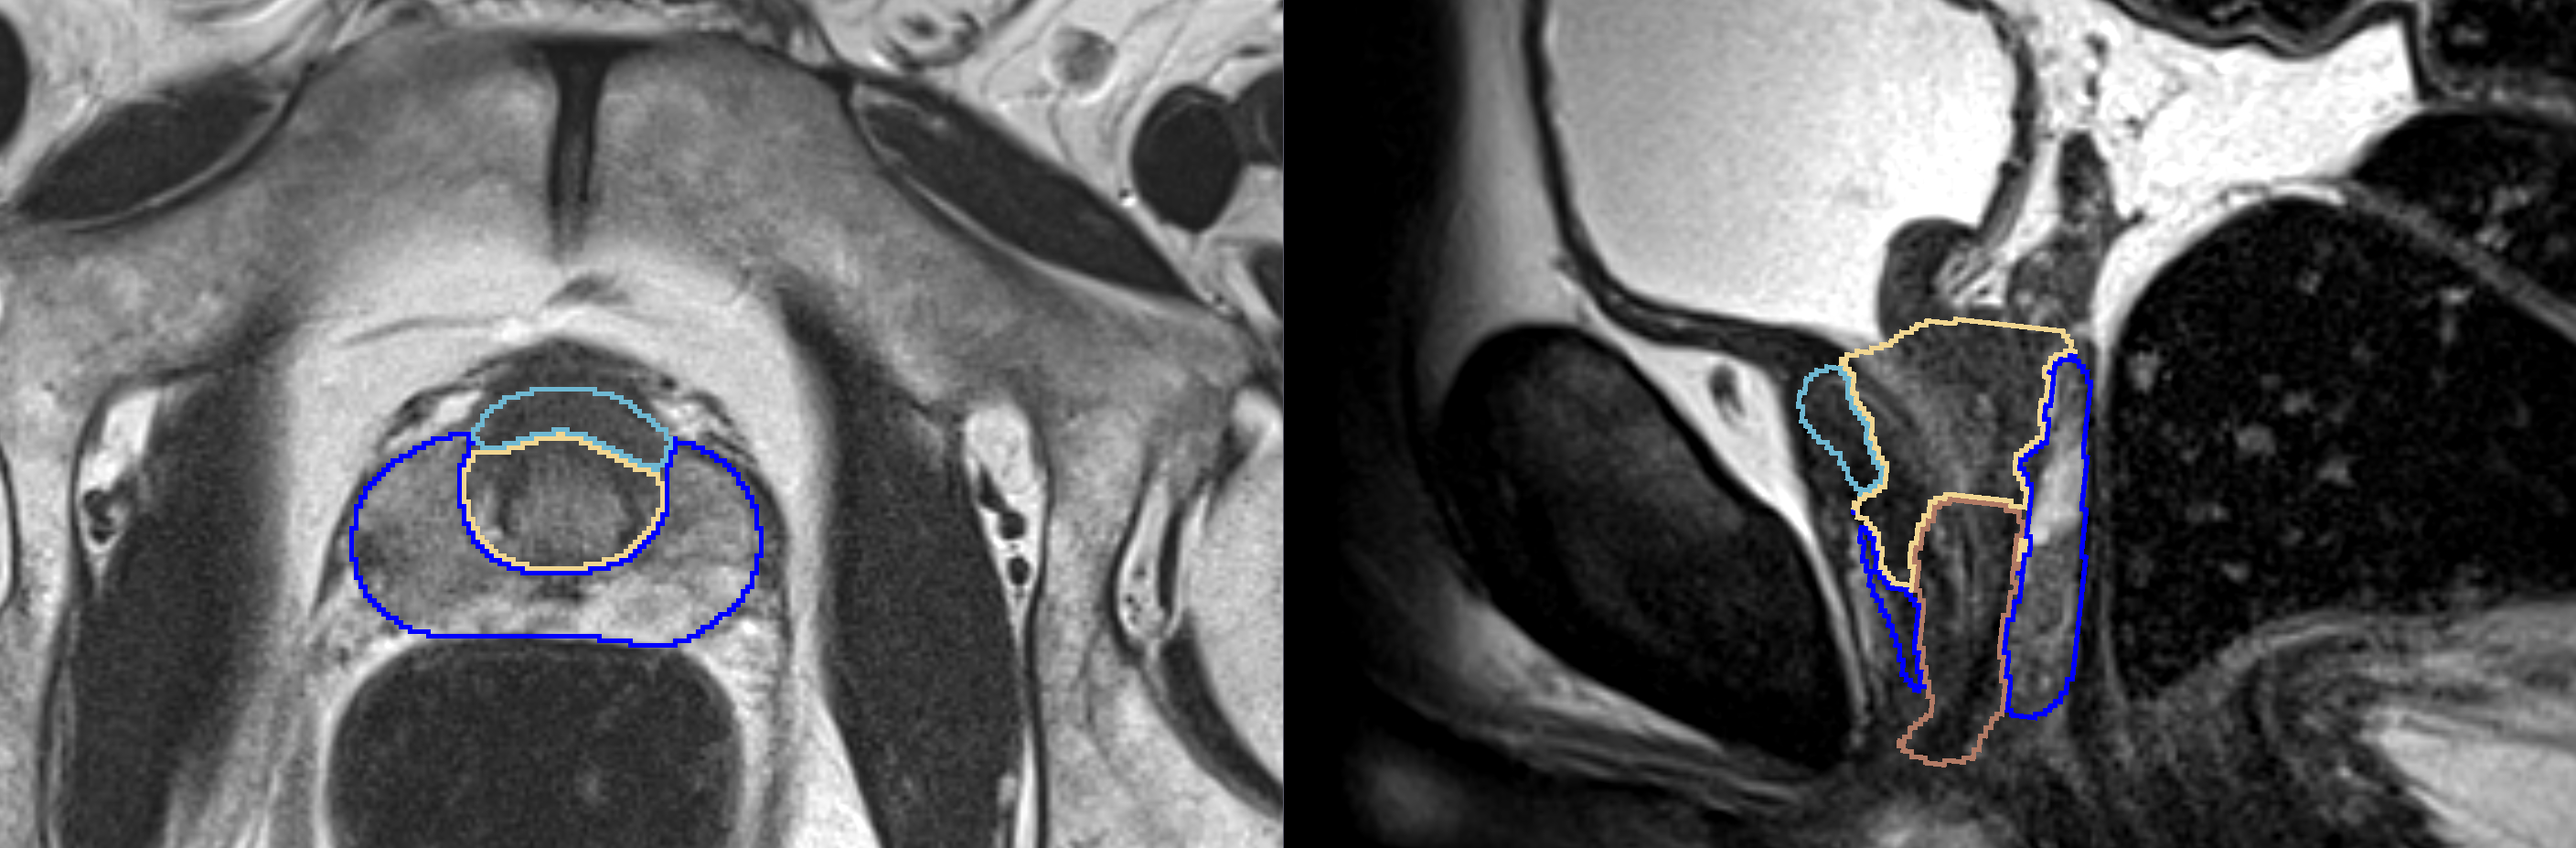

The goal of this project is to create and evaluate variants of a CNN for multi-label segmentation of prostate zones in MR images. The prostate zones are essential for lesion classification and therapy planning.

After successful segmentation, a sector map could be extracted that is used for PI-RADS reporting. This has the potential to automate and better standardize prostate lesion location reporting.

- Improvement of current segmentation result, especially for the anterior fibromuscular stroma (AFS)

- first results on more training data and with different models look promising

- Obtained meaningful results for the AFS .